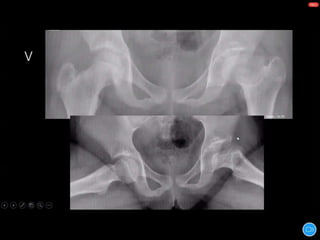

WALDENSTROM STAGES:

1) INITIAL STAGE

2) FRAGMENTATION STAGE

3) REOSSIFICATION STAGE

4) HEALED STAGE